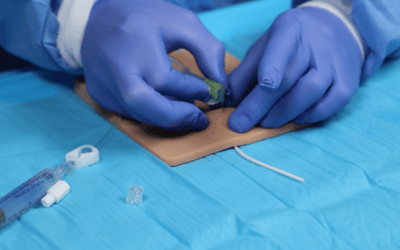

Tras iniciar la exploración del capital venoso, mediante el método RaPeVA (desarrollado por el grupo GAVeCeLT), podemos aplicar el doppler color para identificar y diferenciar las estructuras arteriales y venosas.

Manteniendo la exploración en modo B, activamos el modo doppler color y situamos el ROI o cuadro de color en la estructura que queramos estudiar, asignando un tamaño adecuado al mismo.

Tras iniciar la exploración del capital venoso, mediante el método RaPeVA, podemos aplicar el doppler espectral para identificar y diferenciar las estructuras arteriales y venosas.

Manteniendo la exploración en modo B, activamos el modo doppler espectral. A continuación, colocamos el volumen de muestra (identificado como dos líneas paralelas y perpendiculares al eje del haz de ultrasonidos) en el interior del vaso que se pretende estudiar. El tamaño del volumen de muestra debe ser proporcional al calibre del vaso a estudiar.